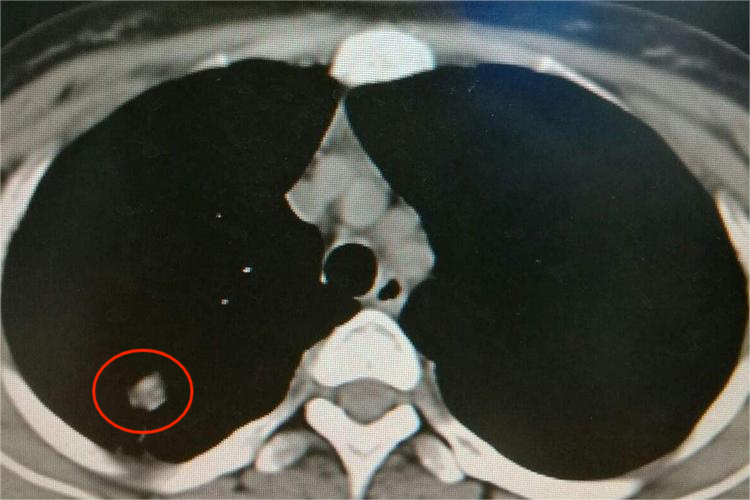

X线和CT表现

X线和CT影像学表现为圆形或椭圆形,单发多见,偶有分叶,密度较高且均匀,常见斑点状或沙粒状钙化,若发现病灶内有层状钙化或裂隙样空洞则为典型所见。同时,病灶周围有斑点状、结节状和条索状卫星灶。